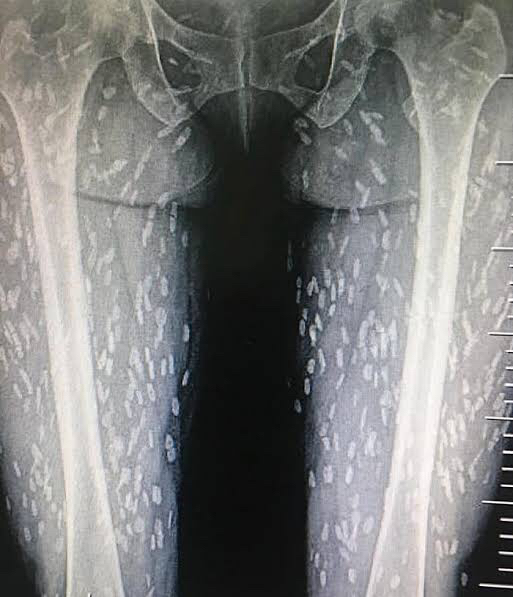

【閲覧注意】寄生虫をレントゲンで撮った画像がヤバすぎる………………

https://i.imgur.com/Dq9jLV8.jpg